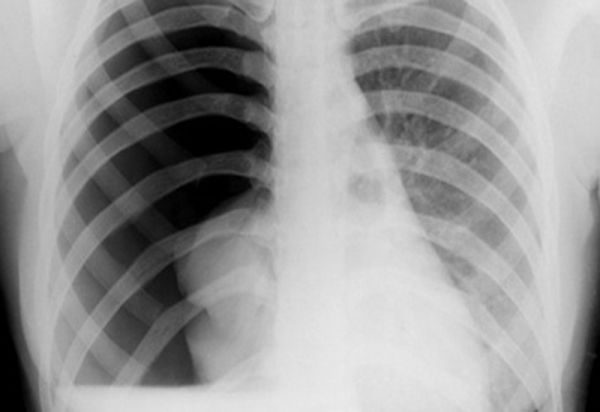

Tràn khí màng phổi trên hình ảnh

Tràn khí màng phổi được định nghĩa là sự hiện diện của không khí hoặc khí trong khoang màng phổi (tức là, không gian giữa màng phổi tạng và thành), có thể làm giảm sự oxy hóa và / hoặc thông khí. Các kết quả lâm sàng phụ thuộc vào mức độ của sự xẹp phổi bên bị ảnh hưởng. Nếu tràn khí màng phổi quan trọng, nó có thể gây ra sự thay đổi của trung thất và sự ổn định huyết động. Không khí có thể nhập vào không gian màng phổi qua từ thành ngực (tức là chấn thương) hoặc thông qua nhu mô phổi qua màng phổi tạng.